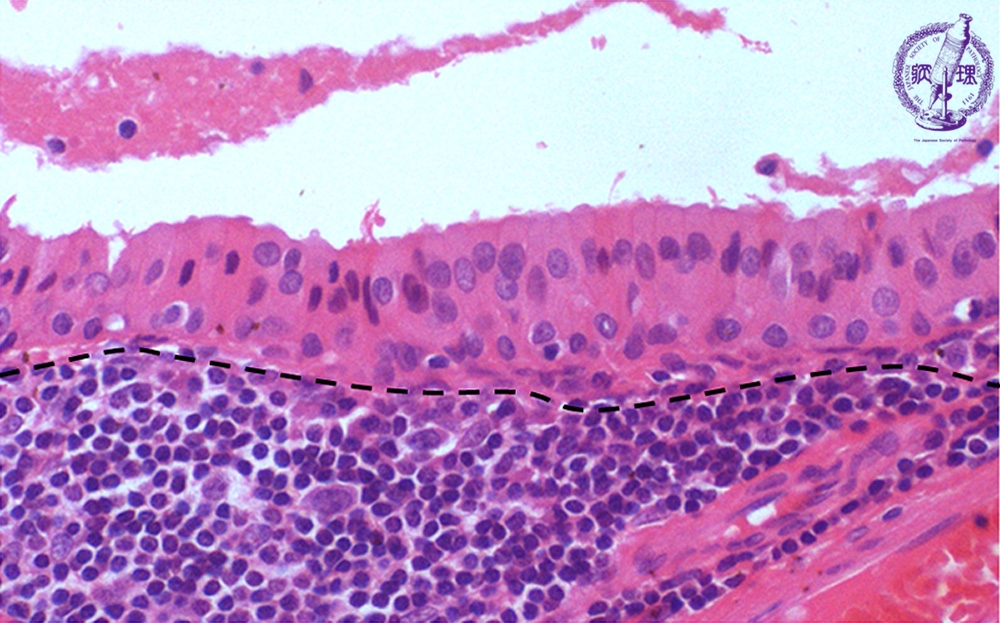

唾液腺腫瘍(ワルチン腫瘍)ミクロ像(HE強拡大)

ミクロ像(HE強拡大):腫瘍細胞は、好酸性顆粒状の細胞質を有するオンコサイトである。腔に面する高円柱状細胞とその下の立方形細胞が2列に並んでいる。間質(点線下方)は、リンパ性組織である。